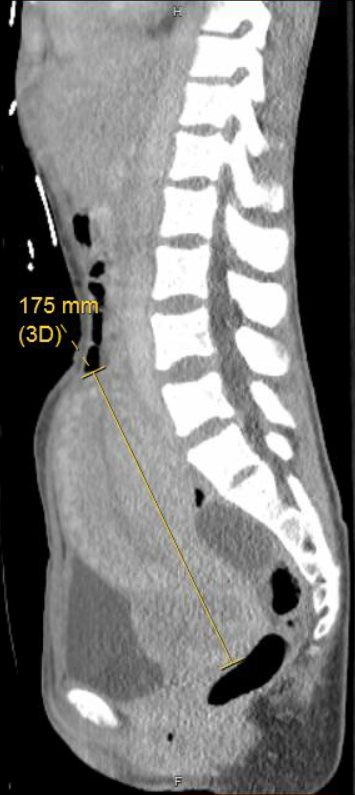

Later that month, the patient presented to our ED for the first time after being found to be minimally conversive at home. Per her family member, the patient had been largely asymptomatic with minor nausea prior to this acute change in mental status. The patient answered yes/no for all questioning with the exception of repeating the phrase “molar pregnancy.” Complete blood count, basic metabolic panel, and Covid-19 tests were normal. A qualitative UPT was negative, thyroid stimulating hormone was 0.01 mIU/L with free T4 of 5.4ng/dL, and urine drug screen was unremarkable. Vital signs were stable aside from sinus tachycardia in the low 100s. Within two hours the patient experienced a generalized tonic clonic seizure. CT head without contrast revealed 3.6x3.3x3.8cm left frontal intraparenchymal hematoma with significant vasogenic edema and a left to right midline shift (Figure 1). TVUS showed a complex intrauterine hypervascular structure. Abdominal CT reveled a markedly enlarged and heterogeneous appearing uterus concerning for malignant process of uterine etiology (Figures 2). An additional large multiloculated cystic structure was identified, centered at the left adnexa with differential diagnosis of complex ovarian cystic mass vs ovarian tumor vs hydrosalpinx. CT chest revealed innumerable nodules throughout the bilateral lungs concerning for metastatic disease (Figure 3). A quantitative b-HCG was >2.5 million with normal cancer markers (CEA of 1.9ng/mL, CA-125 26.80U/mL, AFP 3.7ng/mL), confirming the diagnosis of choriocarcinoma.

Figure 2 Midsagittal view of the uterus.